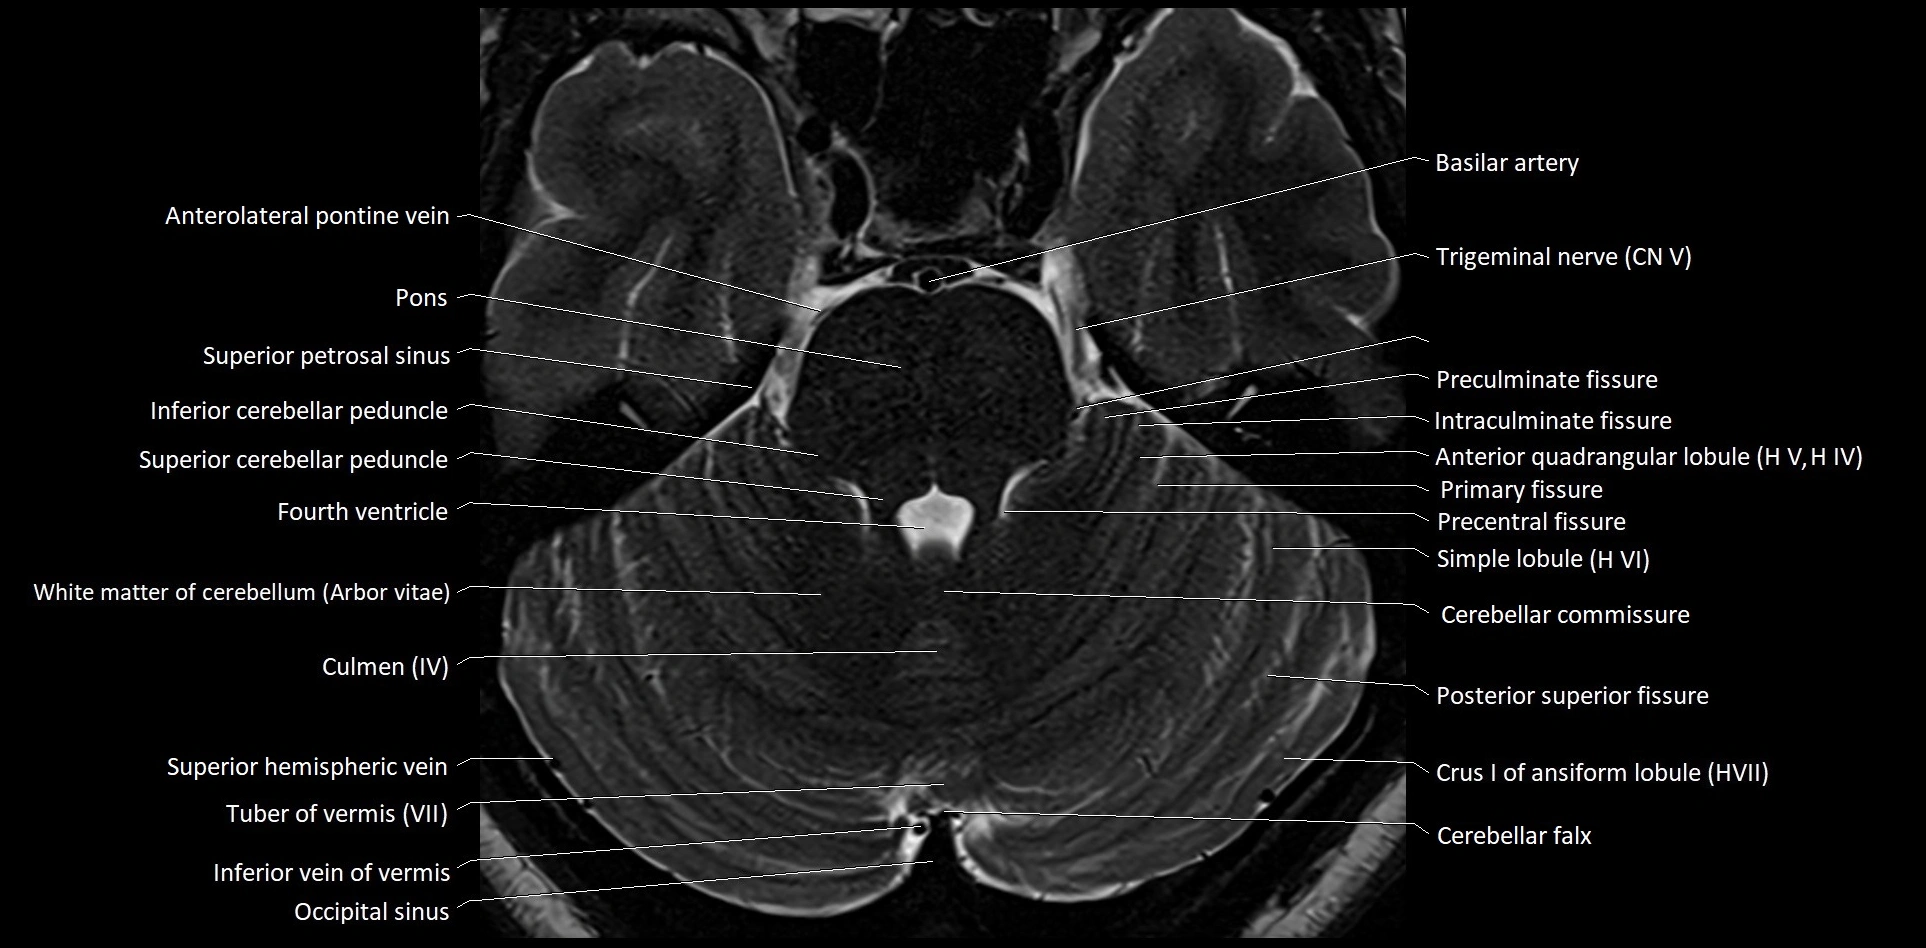

MRI images